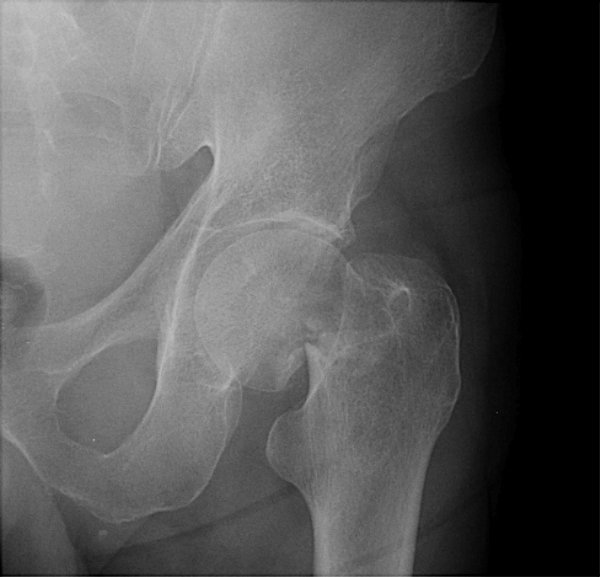

Return to Femoral Neck Fracture